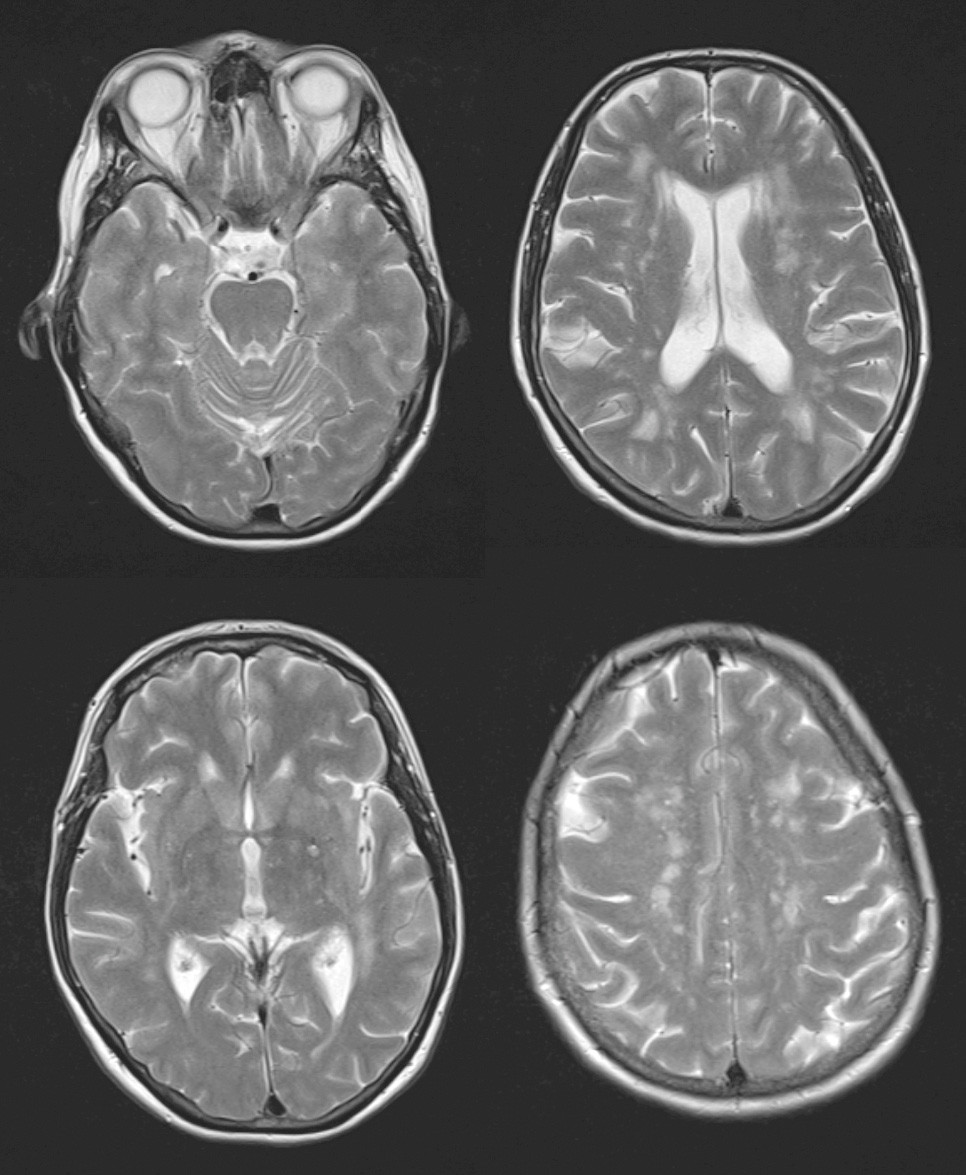

Several population-based studies using MRI scans have revealed an elevated incidence of subclinical stroke in persons with migraine, particularly migraine with aura (17). Some studies have also found an elevated occurrence of non-specific white matter lesions in the brain, while others have not (18, 19) (Fig. 2). However, it has not been possible to show any connection between randomly detected radiological changes of this nature and reduced cognitive function in persons with migraine, and the clinical significance of these findings is uncertain (20).

Figure 2 Axial T2-weighted images show multiple, in part confluent, non-specific white matter lesions periventricularly and…

Figure 2 Axial T2-weighted images show multiple, in part confluent, non-specific white matter lesions periventricularly and subcortically. Images by Unilabs Røntgen Majorstuen, Oslo